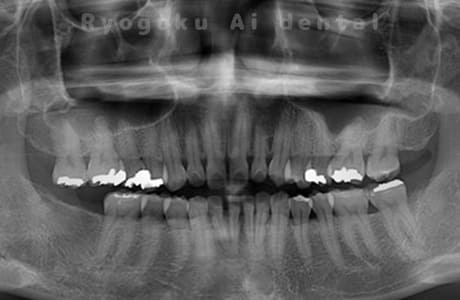

長年、右下からの出血が止まらないということで来院された患者さんです。衛生士さんとのブラッシング指導、並びに、歯石のお掃除を終えても歯周ポケットの改善がなかったため、再生療法を行いました。歯周ポケットが約7ミリ存在した部分が4ミリに改善し、出血もなくなりました。

<リスク・副作用>

手術後は痛み、腫れ、痺れなどの副作用が生じる場合があります。